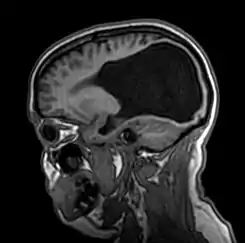

Resonancia magnética en un plano sagital de la cabeza

La colpocefalia es un trastorno en el cual se evidencia un crecimiento anormal de las astas occipitales —la porción posterior de los ventrículos laterales (las cavidades o compartimientos) del cerebro—. Este crecimiento anormal sucede cuando ocurre un subdesarrollo o una falta de espesamiento en la materia blanca del cerebro posterior. La microcefalia (cabeza anormalmente pequeña) y el retraso mental son característicos de una colpocefalia. Otras condiciones incluyen anormalidades motrices, espasmos musculares y convulsiones.